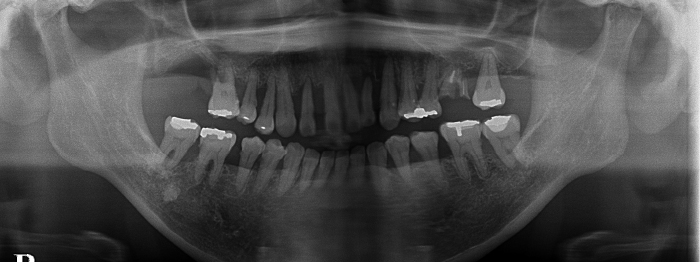

レントゲン写真で再生療法前の右上5番(一番大きい歯の右側の小さい歯)の骨は、かなり急角度でへっています。(青の線)

重度歯周病

レントゲン写真で再生療法4か月後では、同部が増えていることがわかります。(青の線)